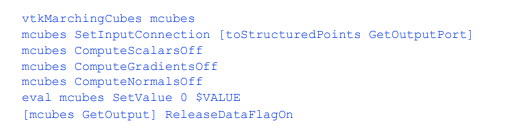

生成的三角形

现在我们可以用移动的立方体来处理体积,就像我们从扫描仪中获得灰度数据一样。我们在管道中添加了一些附加功能。如果我们关闭梯度和普通计算,过滤器运行得更快。移动立方体通常根据体积数据的梯度计算顶点法线。在我们的管道中,我们已经调制了一个灰度表示,随后将抽取三角形网格并平滑产生的顶点。此处理使通过移动立方体计算的法线失效。